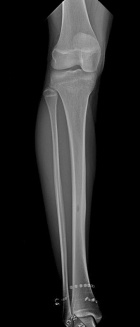

15 yo female with 8 mo h/o aching, right anterior leg pain. C/o of pain at night and with activity alleviated w/ rest and ibuprofen. She denies h/o trauma or constitutional symptoms.

PE: Bony prominence at right anterior tibia w/o notable edema or erythema. Full ROM at knee. NVI. No LAN.